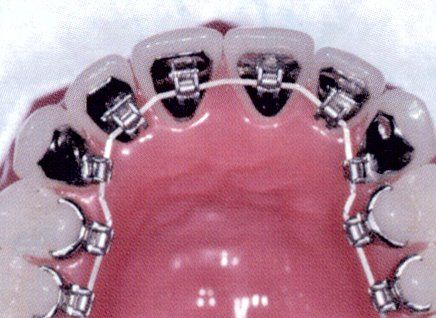

L'ortodonzia dell'adulto è solo ortodontica pura con solo spostamento dei denti, con sistema multi braket estetico trasparente oppure ortodonzia linguale, oppure con mascherine trasparenti (invisalign)

Ci sono vari metodi ortodontici per riuscire a raggiungere un bel sorriso, dall'ortodonzia multi-brackets metallica o trasparente

alla tecnica linguale agli allineatori trasparenti, quest'ultimi nell'ultimo periodo vengono molto richiesti.